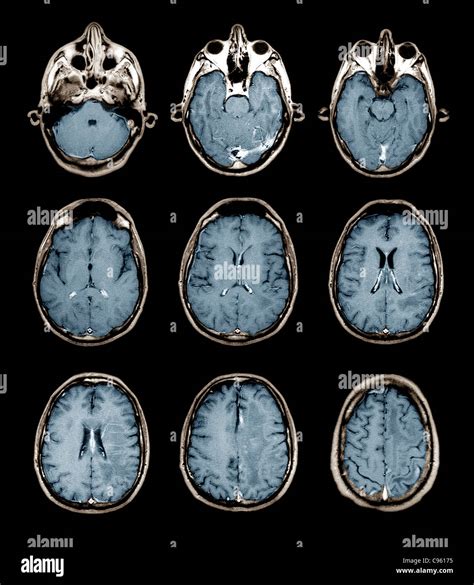

After your brain MRI with contrast is completed, the images are sent to a radiologist—a doctor specialized in interpreting medical scans. They examine the images, comparing the non-contrast and contrast-enhanced sets to identify any anomalies. This analysis is compiled into a formal report, which is then sent to your referring physician. Your doctor will then discuss these results with you, explaining what was found and determining the next steps in your care plan. It is common to feel anxious while waiting for results; however, remember that these scans are intended to provide clarity and guide the most effective treatment path for your unique situation.

• mri brain with contrast images